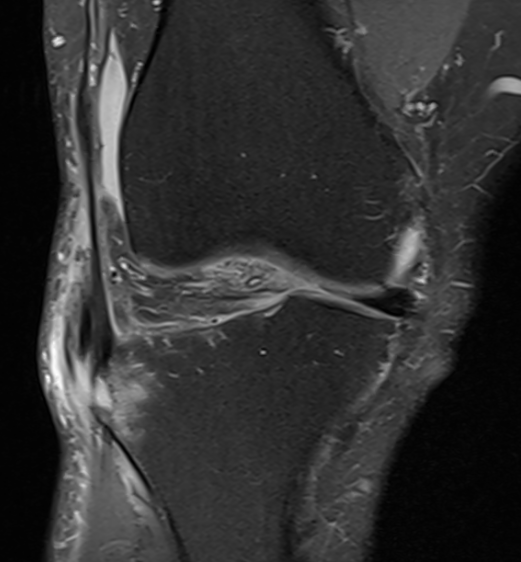

Gerdy's tubercle avulsion injury of iliotibial band